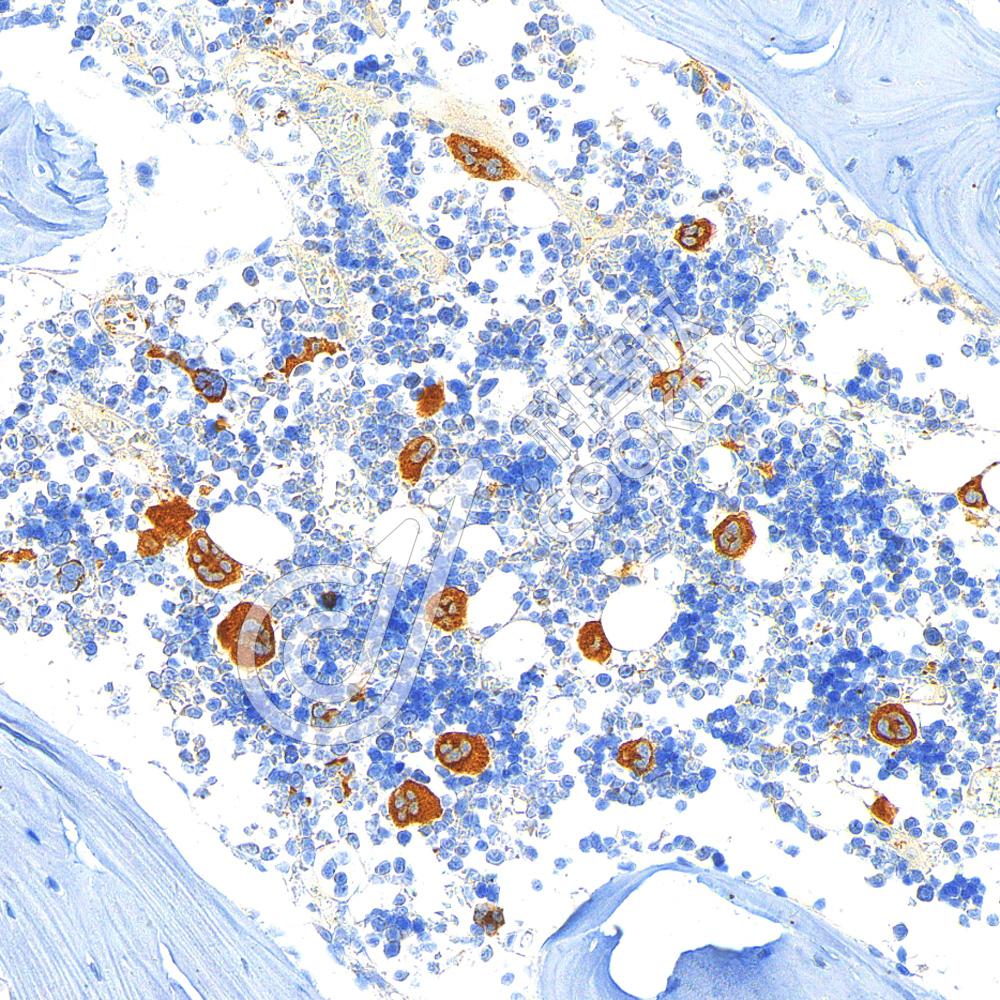

IHC检测TGF beta 1蛋白(货号 K1347217).

样品: 小鼠骨, 4%多聚甲醛 (货号KSG1101) 固定12-24小时.

抗原修复: 柠檬酸抗原修复液(干粉, pH 6.0) (KSG1201), 98℃, 20分钟.

—抗: 1: 800稀释, 4℃ 孵育过夜.

二抗: S-vision免疫组化多聚二抗(山羊抗兔),即用型 (货号KB3906), 室温孵育20分钟.

样品: 大鼠骨关节炎, 4%多聚甲醛 (货号KSG1101) 固定12-24小时.